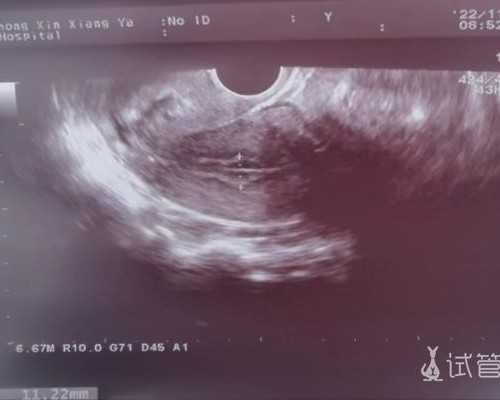

从确定了女性朋友已经怀孕一直到检测之间,这个时间的跨越长度也必须是要满足7周时间的,这是一种硬性的要求是无法被改变的,同时对于孕妈妈腹中胚芽的长度也必须得是要达到10mm才是可以的,如果有的孕妈妈不清楚自己胚芽的长度,那么可以选择找出自己近期的B超单,在这个B超单上面会有关于胚芽长度的记录。

1、一定要确保宝妈在当地的医院进行B超检测,并且单子上面标注有胚芽长度达到了10mm或者10mm以上,并且宝妈的孕期达到了7周或者7周以上。因为通常只有达到7周才能够进行验血检测。